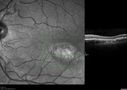

Foveal hypoplasia - aplasia684 viewsSD OCT shows persistent plexiform layers in the center of the macula

EXTENDED HPI: He is having some trouble seeing his gadgets (like his watch). He was diagnosed with morning glory syndrome at about 3 yeras old. This last visit you saw fluid under the retina and asked him to come here. The vision is a little worse.

VA OD: Dcc20/40+2 NccJ2-2

VA OS: Dcc20/25-2 NccJ1-2Dec 20, 2018